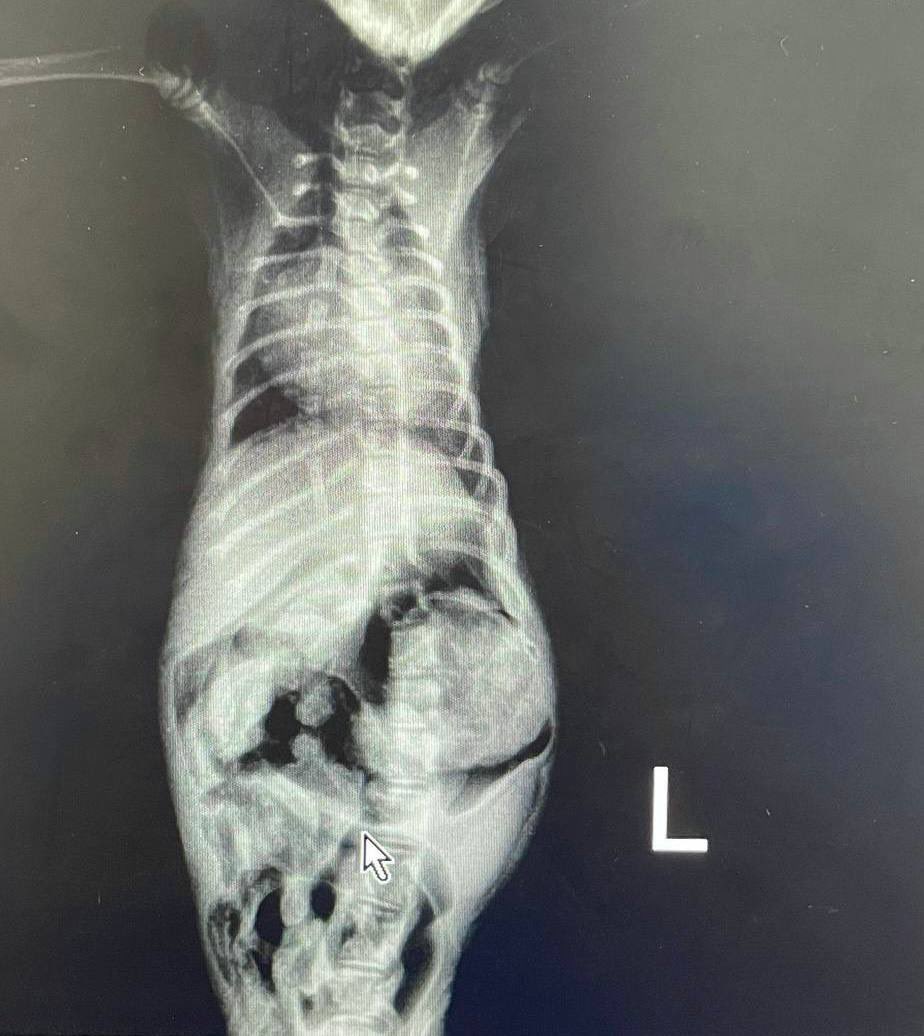

@mgz1995 مرحبا دكتور هل يوجد عندنا مايسمى بعمليه تطويل الاوتار والاربطة ليد هذه القطة بالفيديو؟ ام تبقى على حالها ام بتر ارجو افادتي لو تكرمت